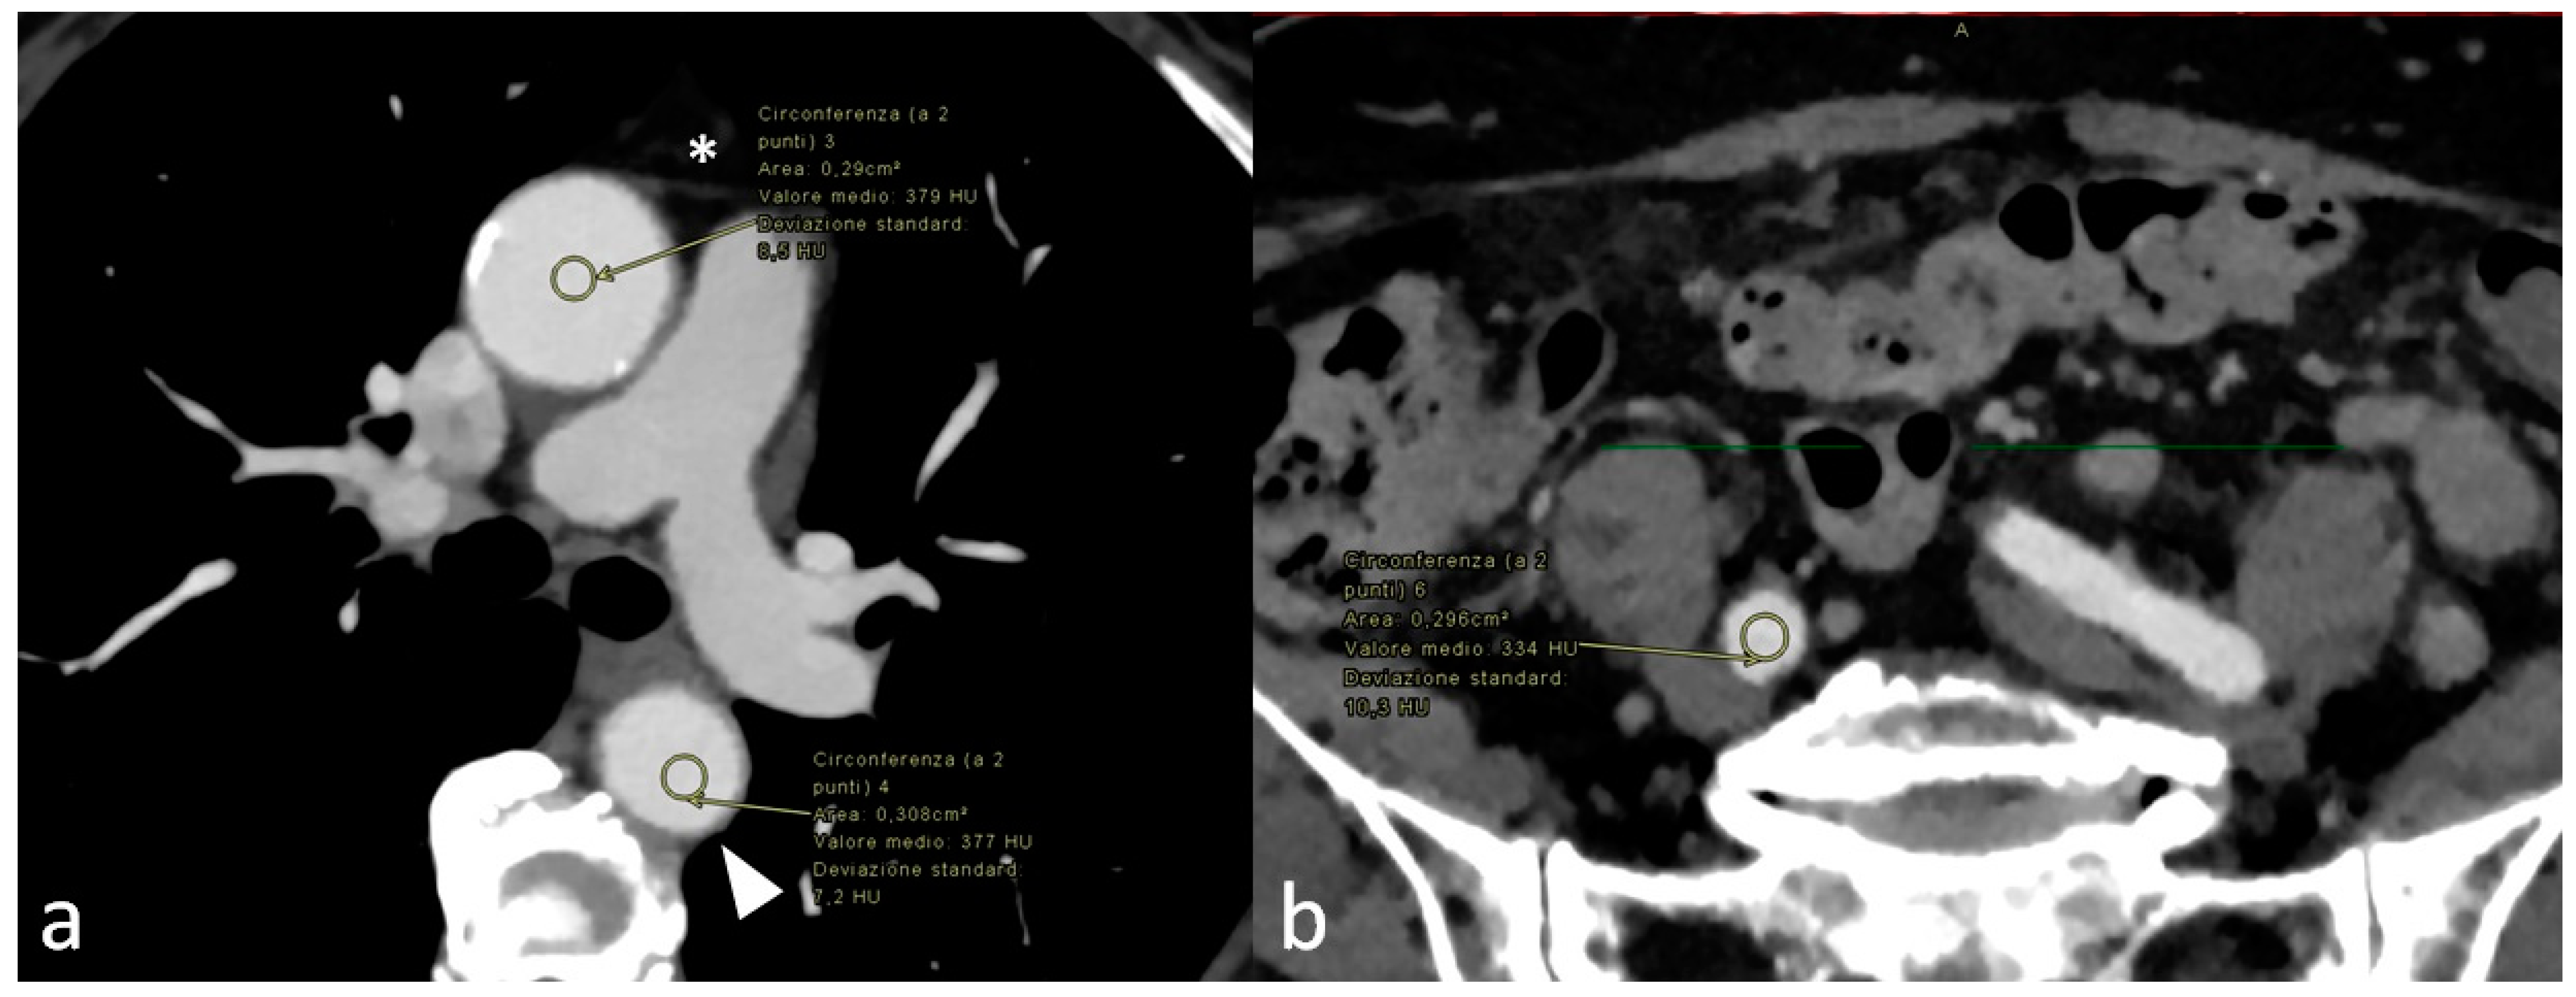

2. Materials and Methods

3. Results

3.2. Quantitative and Qualitative Assessment